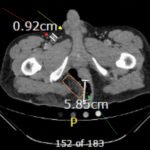

The computed tomography (CT) of the abdomen and pelvis revealed significant subcutaneous gas tracking along the perineum and right gluteal region (orange outline) into the scrotum with associated scrotal edema (yellow arrow) and subcutaneous inflammatory fat stranding of 0.92 cm (red arrow) consistent with Fournier’s gangrene. There is early fluid loculation along the right medial gluteal cleft of 5.85 cm (green arrow) without a sizeable drainable abscess seen.